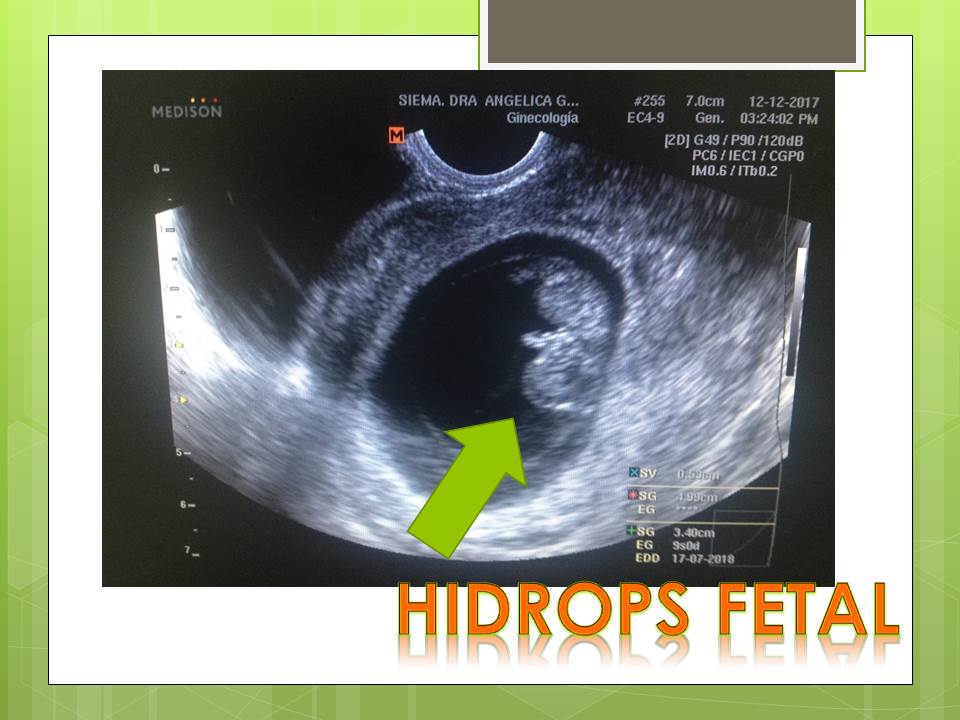

Dra. Angelica (50)

Médico cirujano especialista en Ginecología y Obstetricia - Emprendedora – Amante de la naturaleza – Soñadora – Me gusta el buen vivir